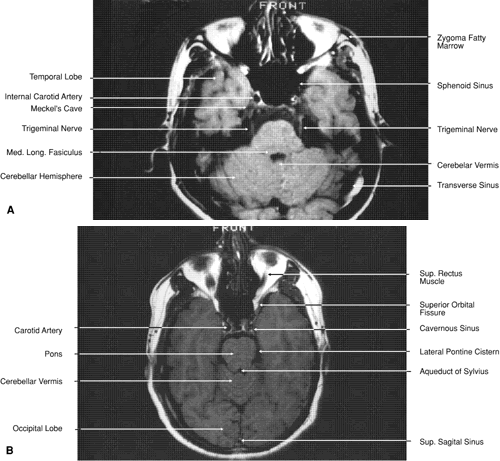

The globe is shown in Figure 12. The orbit and periorbital structures are shown in Figures 13 through 16, and the optic canal is shown in Figures 17 through 26. The cavernous sinus and optic chiasm are shown in Figures 27 and 28, and the posterior visual pathway and cranial nerves are shown in Figures 29 through 33.

Fig. 30. A. Axial T1-weighted image at the level of floor of orbit and trigeminal nerve. B. Axial T1-weighted image at the level of oculomotor nerve.